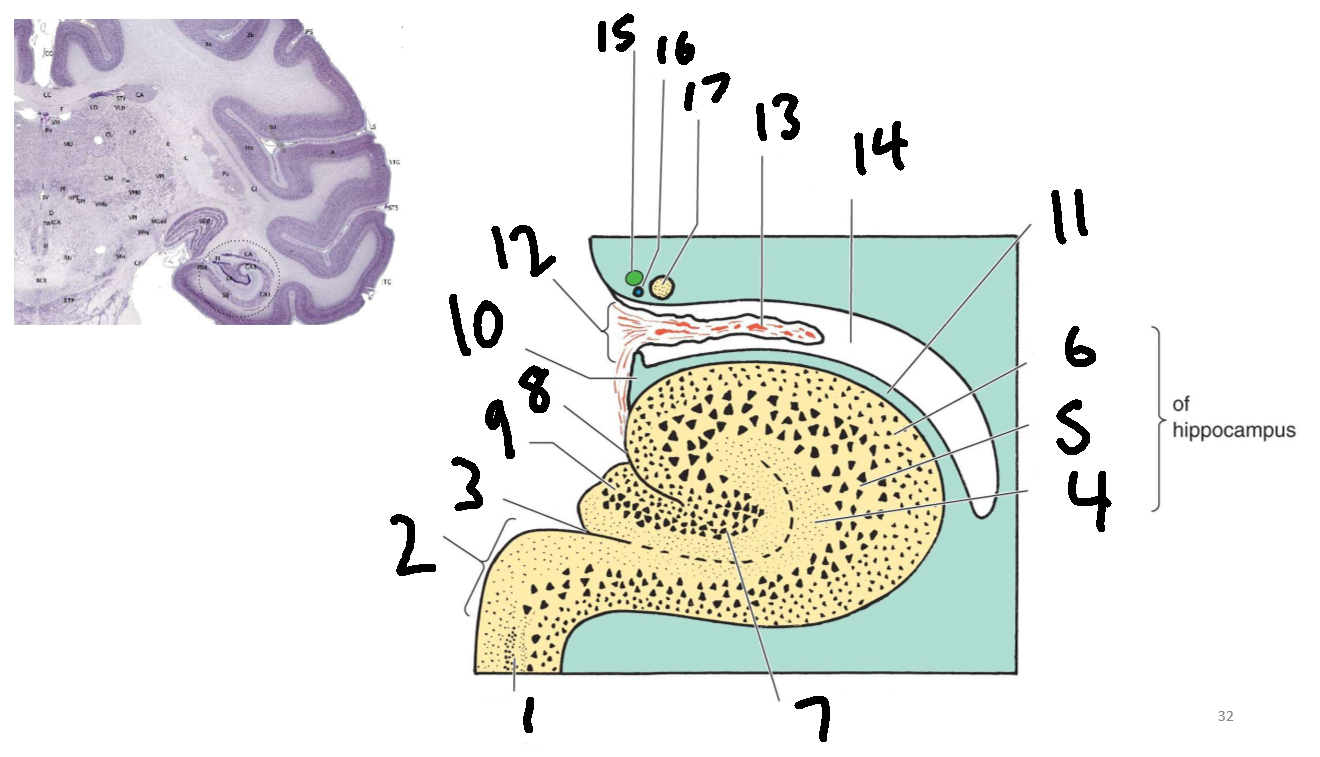

What structure is this?

hippocampus

What is 1?

hippocampus

What is 2?

rhinal sulcus

What is 3?

lateral ventricle

What is 4?

thalamus

What is 5?

entorhinal cortex

What is 6?

perirhinal cortex

What is 7?

parahippocampal cortex

What is 1?

gyrus dentatus

What is 2?

cornu ammonis

What is 3?

fimbria

What is 3’?

alveus

What is the arrow pointing to?

happicampal sulcus

What is ca1, ca2, ca3 and ca4?

fields of cornu ammonis

What is 4?

tela choroidea

What is 5?

stria terminalis

What is 6?

tail of caudate nucleus

What is 7?

temporal horn of lateral ventricle

What is 8?

collateral eminence

What is 9?

collateral sulcus

What is 10?

parahippocampal

What is 11?

entorhinal area

What is 12?

subiculum

What is 13?

lateral geniculate body

What is 1?

parahippocampal gyrus

What is 2?

subiculum

What is 3?

hippocampal sulcus

What is 4?

molecular layer

What is 5?

pyramidal layer

What is 6?

polymorphic cell layer

What is 7?

granule cell layer of dentate gyrus

What is 8?

fimbriodentate sulcus

What is 9?

dentate gyrus

What is 10?

fimbria of hippocampus

What is 11?

alveus

What is 12?

choroid fissure

What is 13?

choroid plexus

What is 14?

temporal horn of lateral ventricle

What is 15?

stria terminalis

What is 16?

thalamostriate vein

What is 17?

tail of caudate nucleus